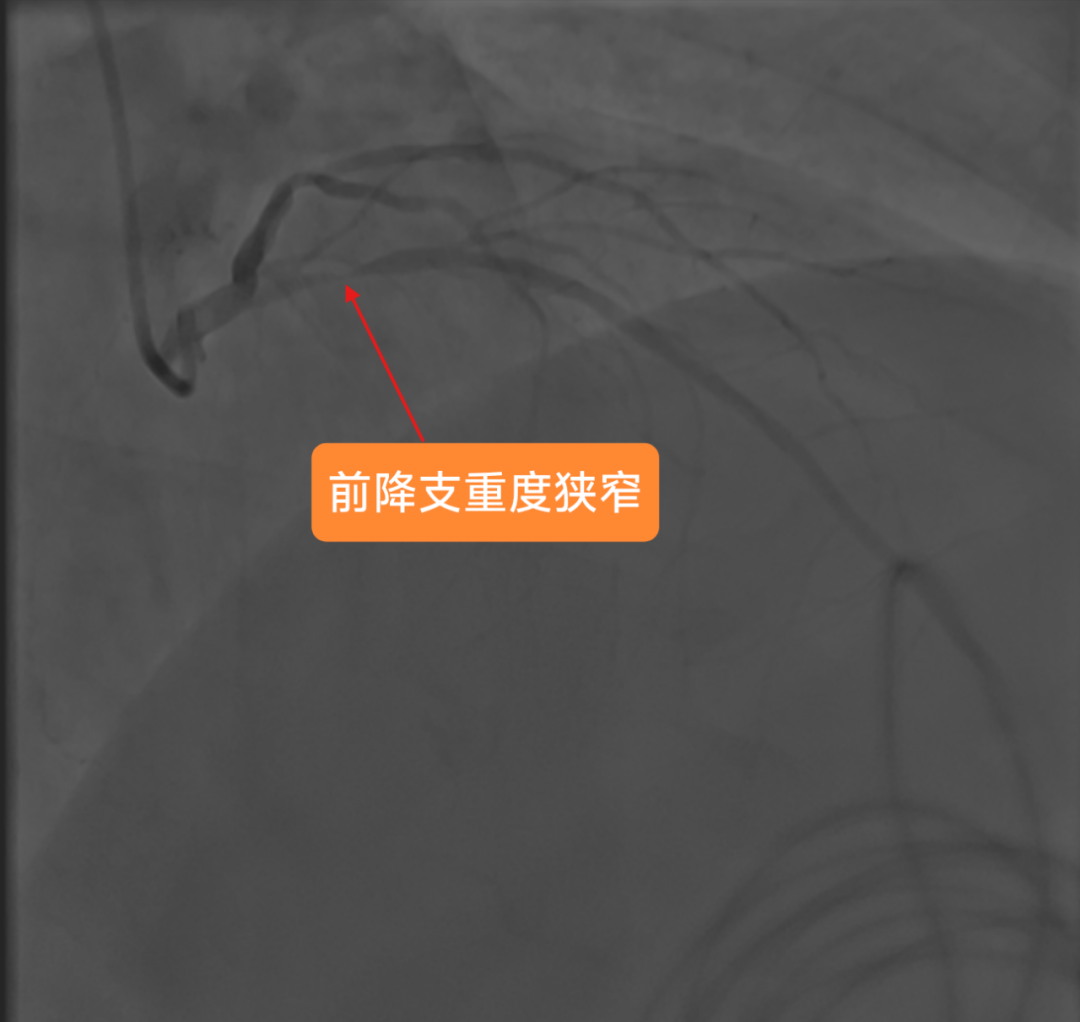

2025年3月4日手术当天,医生穿刺患者右桡动脉进行造影时,一场危象毫无征兆地出现:患者前降支血管近段狭窄达99%,血管近乎完全闭塞。这意味着心脏随时面临因严重缺血而停跳的危险,大脑也承受着巨大且不可逆的缺血性损伤风险,情况刻不容缓,必须立即进行紧急手术,这是挽救患者生命的关键。

冠脉造影显示患者前降支血管重度狭窄